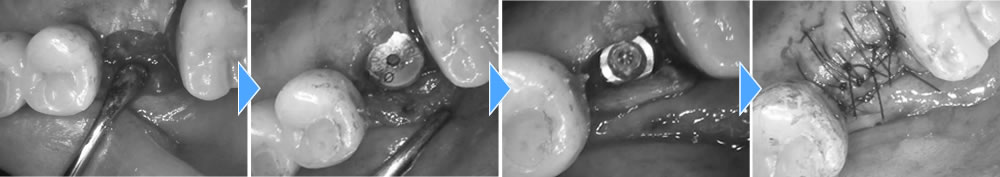

手前にインプラントが入っているため、できるだけ歯茎が下がらないように治療をする事と、CT写真にて上顎洞までの骨の厚みが無い事がわかったので、まずは歯を抜いて骨が落ち着くまで4ヵ月待ちインプラントオペを行う事にしました。

今回は上顎洞までの骨の厚みが足りなかった為に上顎洞粘膜を挙上し、骨を作ると同時にインプラント体を埋入していきました。粘膜を挙上する方法としては水の圧力を利用して行っていきました。

上部構造の装着・治療完了

そこから5ヵ月おき、骨の吸収が無く、骨とインプラント体がオステオインテグレーションしている事を確認し、上部に歯を作成していきました。

結果、横の歯の歯茎が下がりインプラント体が見える事なくしっかりとした歯を作成する事ができました。